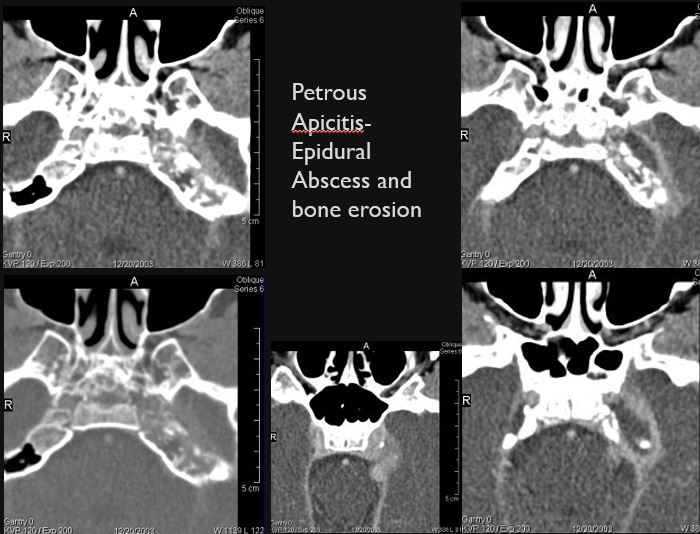

There is an erosive process, subperiosteal or otherwise spreading along the anterior-inferior aspect (extracranial aspect) of the petrous apex involving the bony Eustachian tube and/or carotid canal. [Yes/No]

The petrous apex is abnormal. [Yes/No]

Petrous apicitis associated with middle ear and mastoid disease.

Petrous apicitis with an etiology other than associated with middle ear and mastoid disease.